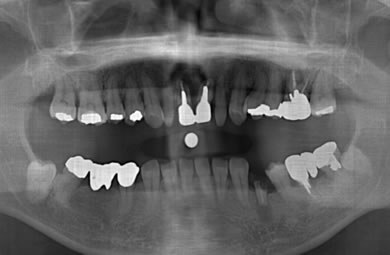

インプラントの症例写真 IMPLANT

骨再生スピードインプラント治療+セラミック治療

| 性別/年齢 | 男性 / 47歳 | ||||||||||||||||||||||||||||||||

| 主訴 | 上の前歯が6ヶ月程前からぐらつき出した。 | ||||||||||||||||||||||||||||||||

| 治療方針 | 審美的・機能的回復をなるべく早くはかる為、抜歯と同時にインプラント治療を行う。また、奥歯に関しては歯周病が進行しているものの、歯の保存が可能な状態である為、エムドゲインを使用し、組織再生をはかる。 | ||||||||||||||||||||||||||||||||

| 治療内容 | インプラント3本(抜歯即日スピードインプラント+GBR)、ハイブリッドセラミック4本、オールセラミックラミネートベニア2本、エムゲドイン組織再生療法 | ||||||||||||||||||||||||||||||||